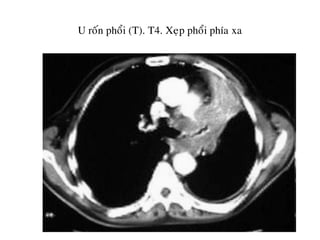

U roán phoåi (T). T4. Xeïp phoåi phía xa

Haïch döôùi carina